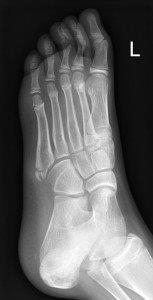

Avulsion fracture of base of fifth metatarsal

- Follow up Orthopaedic Fracture clinic 7- 10 days.

- If 4th and 5th inter-metatarsal joint involved (Jones Fracture), not suitable for CAM Boot.

Single and multiple non-displaced metatarsal fractures

- Follow up Orthopaedic fracture clinic in 7 - 10 days.